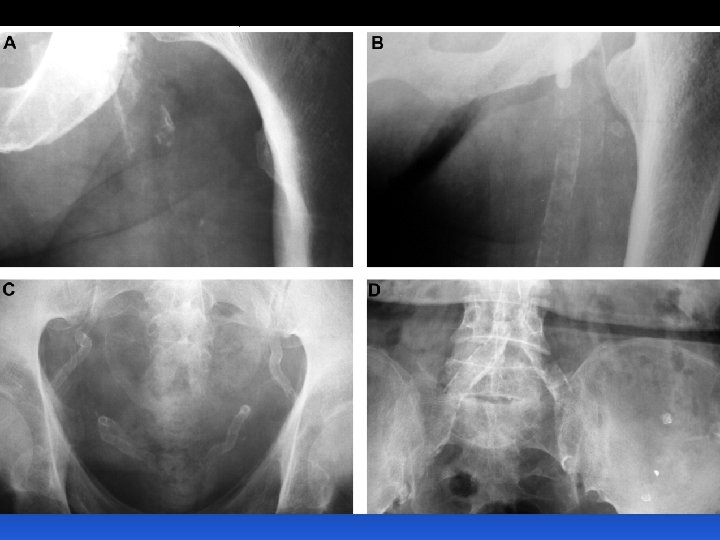

STADI MALATTIA RENALE e CARDIOVASCOLARE Insuff. Renale cronica terminale Insuff. Renale Cronica ( FG) Albuminuria Proteinuria Anziano, obesità Diabete Mellito, Press. Arter. Malattia Renale Cronica Stadio Scompenso cardiaco finale Progressione Eventi malattia cardiovascolare (MCV) MC Insuff. Ventricolare sx Inizio “A rischio” Anziano, obesità Diabete Mellito, Press. Arter. Malattia Cardiovascolare Sarnak MJ & Levey AS, Am J Kidney Dis, 2000

Il rischio della malattia renale cronica va ben al di là del rene Rischio Relativo 3. 4 4 2. 8 3 2 2 1. 4 1 0 No lieve/moderata/severa insufficienza renale avanzata